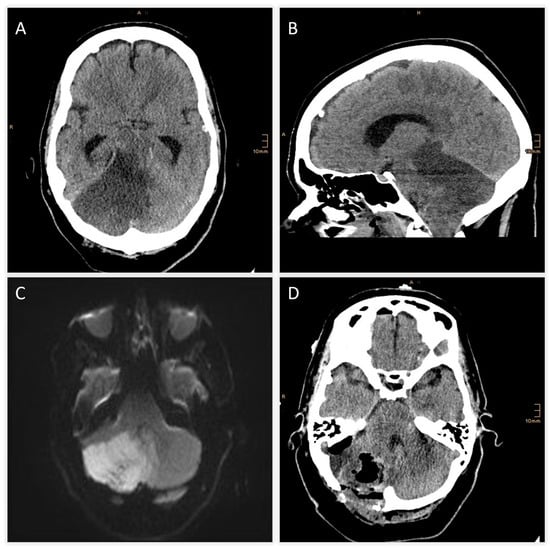

| +2 h (admission) | Initial MRI (DWI) + TOF-angiography | Acute infarction of right cerebellum and vermis; thrombus at basilar tip; right SCA occlusion |

| +6 h | CT scan | Expanding right cerebellar infarct with mass effect; apparent hypodensity in pons, midbrain, diencephalon → suspicious for brainstem infarction |

| +7 h | MRI follow-up | Brainstem infarction excluded; predominant cerebellar edema confirmed |